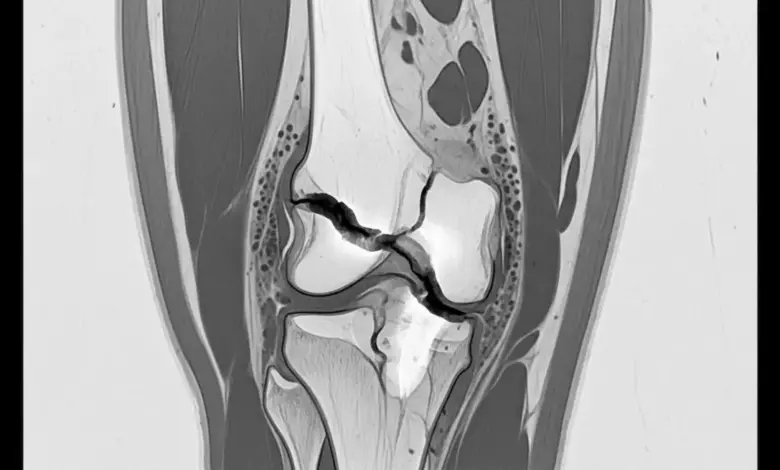

A cirurgia de patela com fios costuma entrar na conversa quando a fratura muda o alinhamento da patela e o joelho perde parte da sua função.

A cirurgia é considerada quando há perda da congruência articular, afastamento dos fragmentos ou falha do mecanismo extensor.

Nesses quadros, deixar a fratura sem estabilização pode comprometer o desempenho do joelho no médio e no longo prazo.